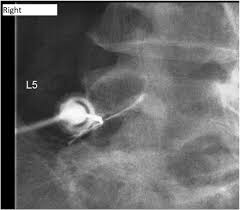

Epidural steroid injections are usually limited to just a few a year because there's a chance these drugs might weaken your spinal bones and nearby muscles. Cortisone injections may be given up to four times a year per affected joint. Cortisone injections can be helpful for patients with rheumatoid arthritis. 3 to improve the overall outcome of the procedure and reduce the risk of side effects, using a blunt needle, live fluoroscopy, and administering a small test dose initially may be helpful. Repeated cortisone injections are not healthy for tissues. This isn't caused by the needle — it's a possible side effect of steroids. For chronic conditions, three to six months or more between injections is common. No more than three cortisone shots in the space of a year is a typical number that many orthopedic surgeons use. Epidural steroid injections are recommended to be administered up to three to six times per year. Cortisone shots may be given for conditions such as tennis elbow. However, other experts believe that up to 6 injections per year is safe. In the case of a new disc herniation, injections may be only weeks apart with a goal of quick and complete resolution of symptoms. Medicare will cover epidural steroid injections as long as they're necessary.